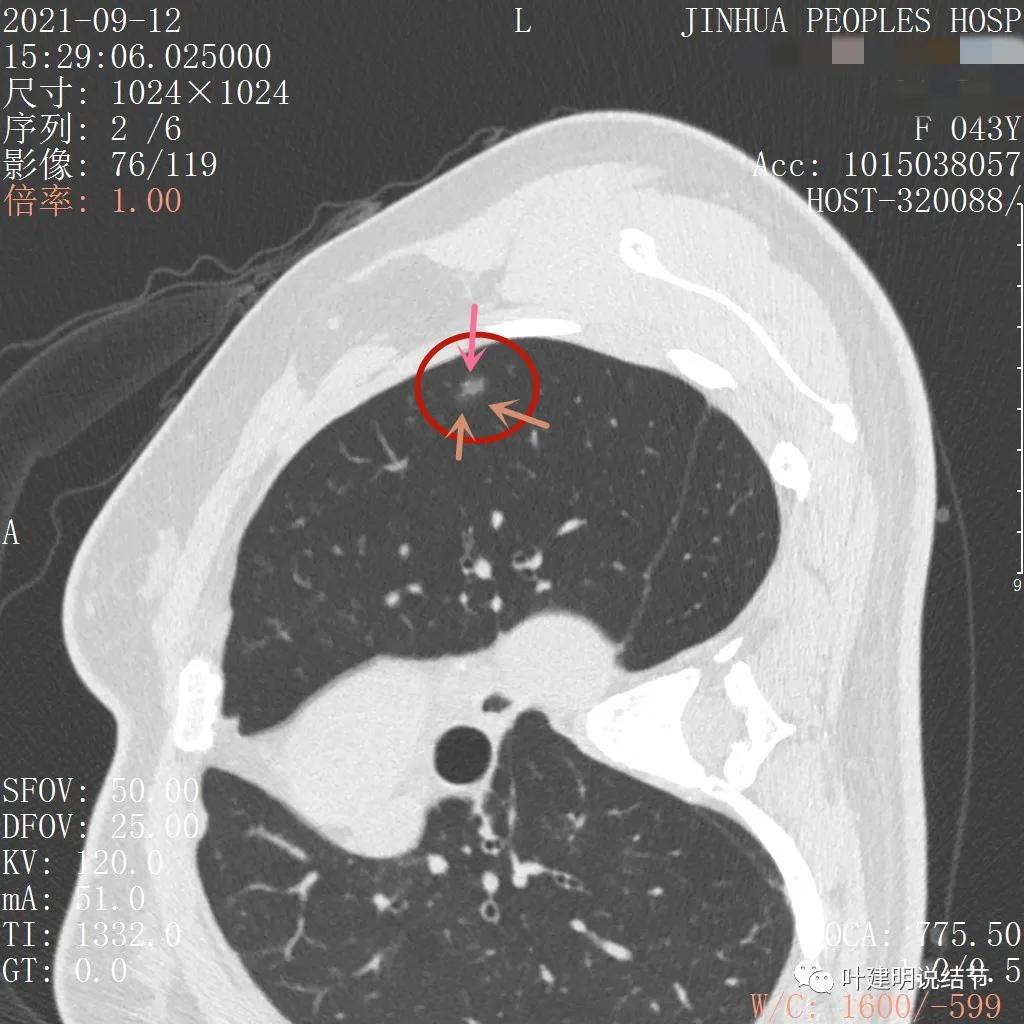

上图示病灶内部有高密度点状成分(粉色箭头所指)

同样示内部点状高密度,瘤肺边界清,密度显乱

上图显示混合磨玻璃结节,中间点状高密度区域,边上有微小血管征

上图示病灶边缘磨玻璃成分有的区域密度过低(绿色箭头),事后回头来看,磨玻璃部分的密度过低,不容易是浸润性腺癌,而更符合原位腺癌

上图示瘤肺边界处显模糊(砖色箭头),病灶内部仍是有偏高密度的点状成分